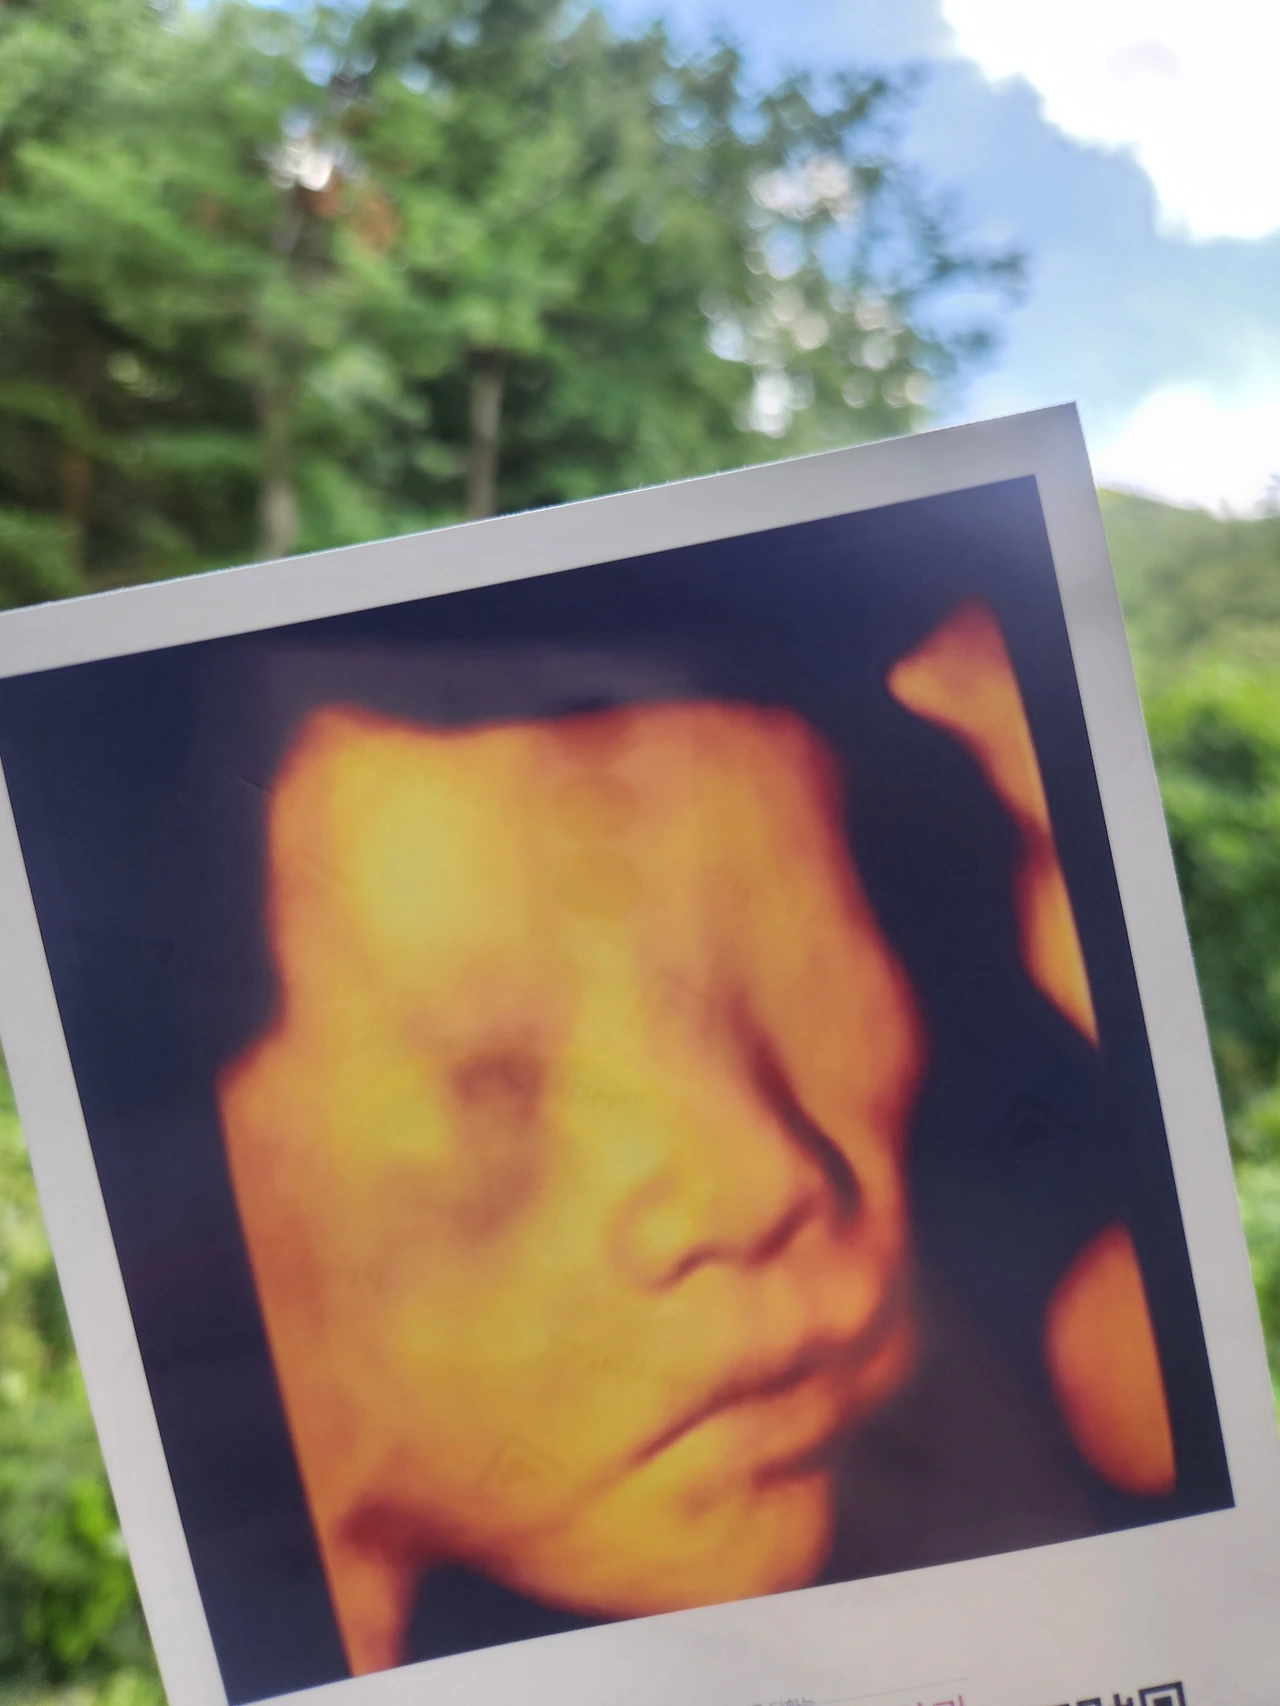

우리 호두가 정말 너무너무 기특했어. 오늘은 호두 얼굴도 좀 볼 수 있었어.

한 달 전 초음파 검사랑 마찬가지로 두 팔을 얼굴 옆에 올리고 있어서 완전 잘 보인 건 아니었지만 그래도 저번보다는 더 잘 볼 수 있었어. 호두가 입도 막 뻐끔거리고 다시 생각해도 감격스러워서 눈물이 나네. 팔도 막 움직이고 엄청 활발하게 움직이고 있었어. 선생님도 '아기가 엄청 활발하네요. 태동 많이 느껴지시겠어요.'라고 하실 정도였어.